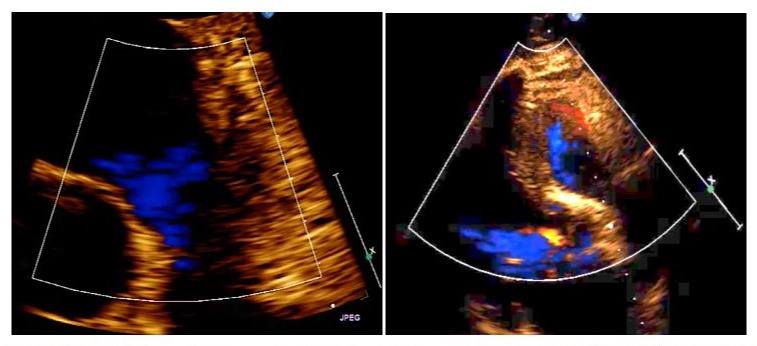

With an initial diagnosis of a mass in the right ventricular outflow tract (possible thrombus), the following are performed: Ecotranseophageal, where an echodense mass of 2.5 cm is better appreciated, rounded and with clear limits, with an anchoring in the anterior face of RVOT and that protrudes in each systole to the trunk of the pulmonary artery, regressing in the diastole to the RVOT, with negligible valve regurgitation (possible diagnosis: myxoma in RVOT). CT-angiography shows a hypodense mass in RVOT, adhered to its wall and protruding through the pulmonary valve, with normal trunk, pulmonary arterial branches and parenchyma, and no debris suggesting pulmonary embolisms (a very probable myxoma diagnosis). MRI shows a 20 mm pedunculated mass in RVOT, a slight increase in the signal in T1 and a slight decrease in T2, with moderate prograsive uptake of with gallodinium contrast, for which the radiologist gives us these three diagnoses in decreasing order of suspicion: cardiac papillary fibroelastoma, slow flow hemangioma and myxoma (Figure 3).

Figure 3: Right ventricular outflow tract (RVOT) MRI T1 with contrast, showing the right ventricular outflow tract (RVOT), the trunk of the pulmonary artery and the pulmonary valve with an obstructive tumour.